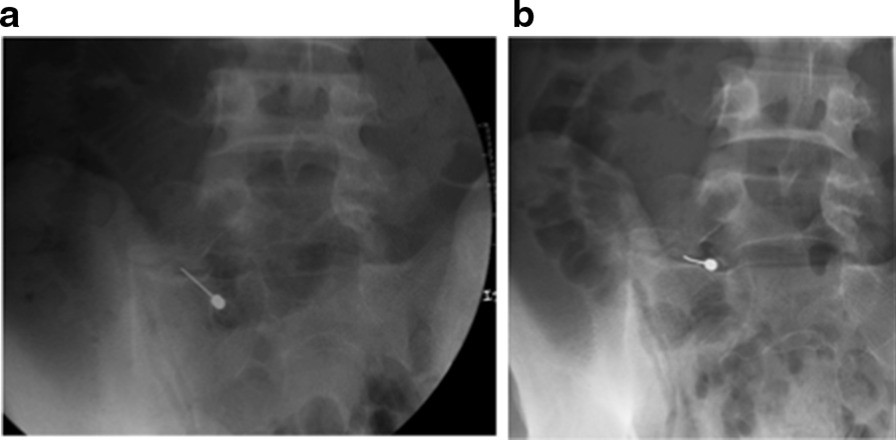

Fig. 2From: The effectiveness of preoperative assessment using a patient-specific three-dimensional pseudoarticulation model for minimally invasive posterior resection in a patient with Bertolotti’s syndrome: a case reportAnesthetic injection during pseudoarticulationBack to article page